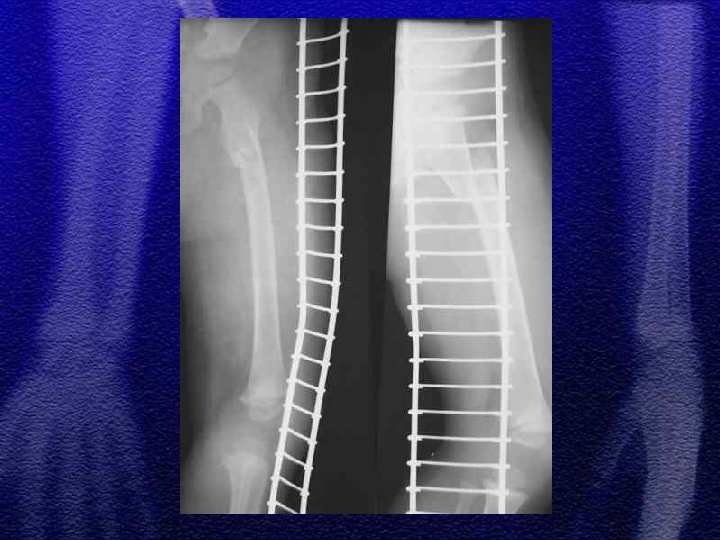

§ Do 4 roku życia leczenie wyłącznie zachowawczewyciąg plastrowy lub szkieletowy w zależności od wieku § Większość złamań do 10 r. ż. - wyciąg szkieletowy ok. 3 tyg. , a następnie gips biodrowy od 3 do 6 tygodni w zależności od wieku § Leczenie operacyjne rozważa się po 10 roku życia a metody zespolenia to: Zespol, pręty Endera, Rusha, stabilizatory zewnętrzne